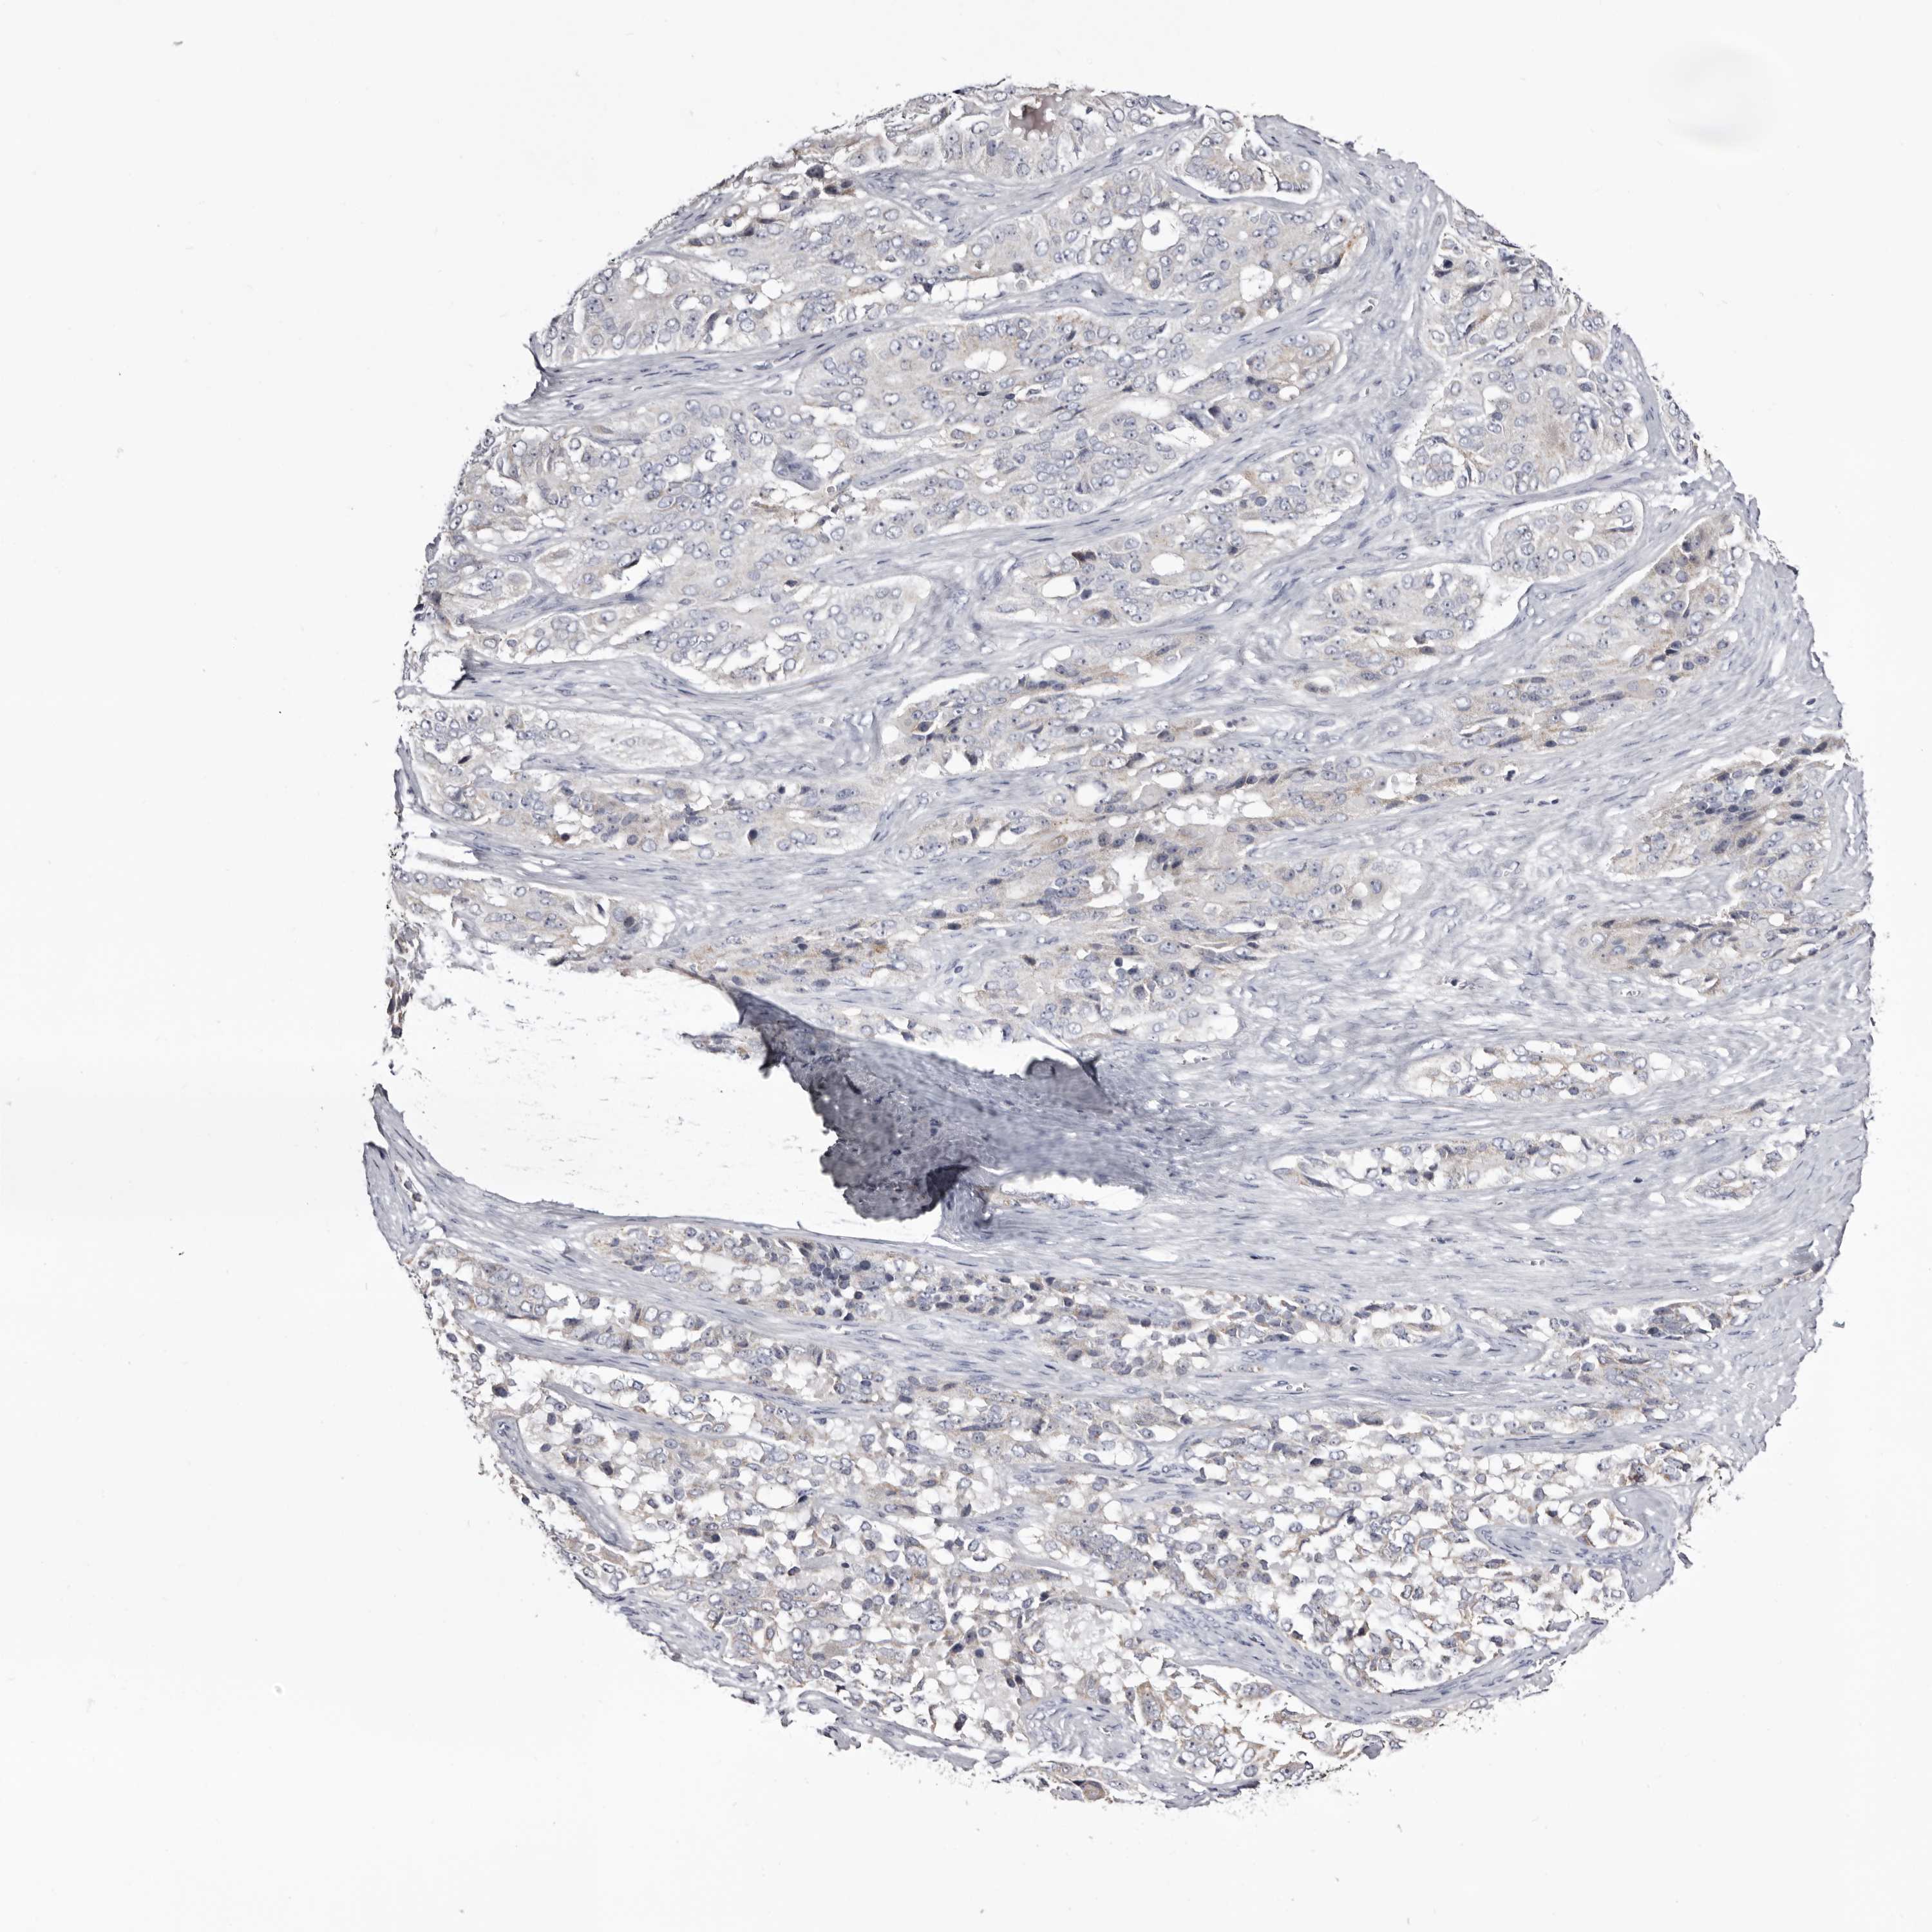

OVARIAN CANCER - Protein expressioni

A mouse-over function shows sample information and annotation data. Click on an image to view it in a full screen mode. Samples can be filtered based on level of antibody staining by selecting one or several of the following categories: high, medium, low and not detected. The assay and annotation is described here.

Note that samples used for immunohistochemistry by the Human Protein Atlas do not correspond to samples in the TCGA dataset.

Antibody stainingi

Antibody staining in the annotated cell types in the current human tissue is reported as not detected, low, medium, or high, based on conventional immunohistochemistry profiling in selected tissues. This score is based on the combination of the staining intensity and fraction of stained cells.

Each image is clickable and will lead to virtual microscopy that enables deeper exploration of all samples and also displays staining intensity scores, fraction scores and subcellular localization as well as patient and tissue information for each sample.

Antibody HPA007845

Antibody HPA026823

Antibody CAB015170

Cystadenocarcinoma, serous, NOS

Carcinoma, endometroid

Cystadenocarcinoma, mucinous, NOS

Carcinoma, NOS